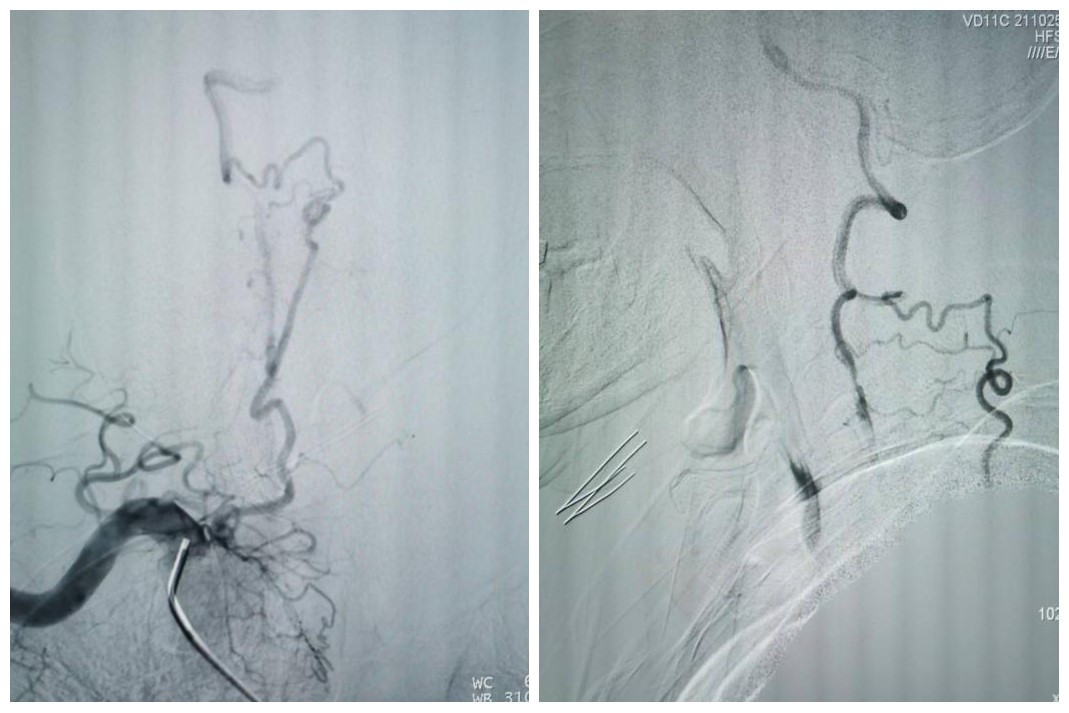

患者拜某,男,65岁,因反复头晕、晕厥1年,加重10天入院,既往5年前因心肌梗死在外院冠脉植入5枚支架。本次发病后当地医院发现患者脑后部的主干动脉——双侧椎动脉在颈部完全闭塞,当地医院药物医治无效,患者慕名从商洛来到我院神经内科。入院后经过脑血管造影发现患者双侧椎动脉颈部闭塞段大约10cm,闭塞远端经过甲状颈干及肋颈干向V2近颅底以远代偿供血,但因代偿不足,患者近来反复脑梗死2次,此次入院再次提示小脑新鲜脑梗死。

受呼吸起伏波动的影响,椎动脉开口狭窄是动脉粥样硬化好发的部位之一,也是支架成形术后支架内再狭窄的好发部位。这个短小的病变对于神经介入医师来说,常常是最青睐的支架手术部位。然而,该患者延伸至V2远端的长节段慢性闭塞病变,闭塞长度接近10cm,尤其是闭塞近段无残端的病变,常常会成为脑与心脏之间的“天堑”,使神经介入医师望而却步,即使眼看着患者的临床病情在进展,常常也是束手无策。

最终,在患者入院第4天,张桂莲教授带领的介入团队选择局麻条件下为患者成功实施了神经介入领域的高难度手术—左侧无残端椎动脉长节段慢性闭塞再通术。因术前清晰的影像显影及准确的体外定位标记,左侧优势椎动脉顺利开通,手术耗时仅仅约90分钟。术中及术后患者配合良好,无任何不适,术后在介入准备室,张桂莲教授向患者女儿详细告知手术过程及患者目前状况,患者女儿喜极而泣,多次向介入团队表示感谢。

双侧椎动脉闭塞是“天堑”,其所导致的后循环缺血事件是“天灾”,严重影响患者生活质量,甚至随时危及患者生命。无残端的双侧椎动脉慢性闭塞再通,是神经介入领域的最高难度手术之一,其原因在于根本无法确定手术位点。面对患者及家属的信任,我院张桂莲主任领导的神经内科介入团队与李晓会教授带领的影像学团队不忘初心、紧密合作、敢于挑战、乐于奉献,最终不负患者及家属重托将无残端长节段椎动脉闭塞的“天堑”变为后循环正常血流的“通途”。